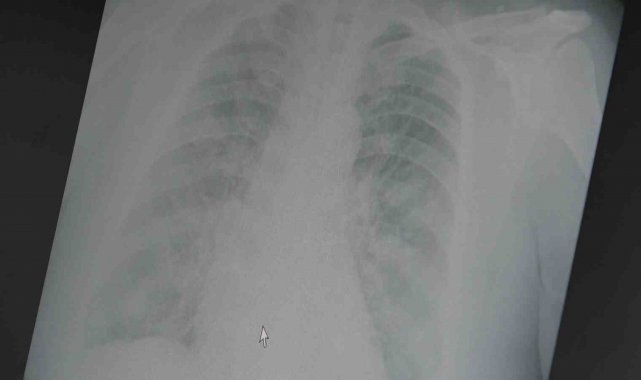

Sezon sonu raporlarına göre bu yıl grip aşıları yetişkinlerde hastalığı önlemede yüzde 25 ila yüzde 30 oranında etkili olduğunu söyleyen Prof. Dr. Şevket Özkaya açıklamalarda bulundu. Bu durumun son 20 yıldaki en düşük etkinlik oranlarından biri olduğunu ifade eden Prof. Dr. Özkaya, erken hakim olan yeni suşun aşının içeriğiyle iyi eşleşmemesinin yoğun grip vakalarına yol açtığını vurguladı.

Yeni suşun A H3N2 tipi olduğunu ve kolay yayıldığını belirten Prof. Dr. Özkaya, "Her ne kadar grip aşılarının koruyucu etkinliği azalmış olsa da, ciddi hastalık ve ölümleri önlemede aşının önemi sürüyor. Grip aşısı yaptırmak hâlâ değerli" dedi.

Prof. Dr. Özkaya, pandemi sonrası grip aşılarının etkinliğinin genel olarak azaldığını ve düşük aşılama oranlarının da etkili olduğunu belirterek, önümüzdeki mevsim için yeni suşları kapsayan aşıların piyasaya çıkmasını beklediklerini sözlerine ekledi.